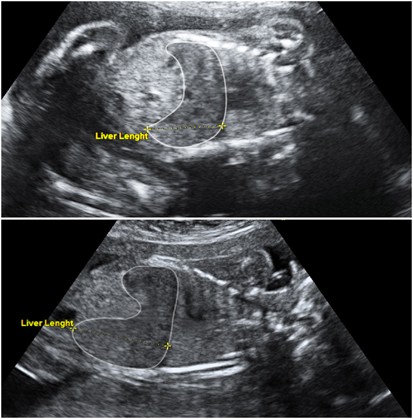

Recently, a 33-year-old woman came to the doctor for treatment. Doctors performed an ultrasound and confirmed that the woman was pregnant. However, the ultrasound report surprised the doctors as well as the woman. The thing is that even though the woman was pregnant, the doctors noticed that the baby was growing in her liver rather than in her womb.

Doctors after checking said the woman had an ectopic pregnancy in her liver. An ectopic pregnancy occurs when the egg begins to travel in the wrong direction in the fallopian tubes. Due to this, the pregnancy does not go well. It appears many times in the stomach, but for the first time, it appears in the liver.

Doctors who noticed it immediately operated on the woman and her life was saved. But the fetus had already died in the liver. In such a situation the doctors removed the dead fetus from the liver.